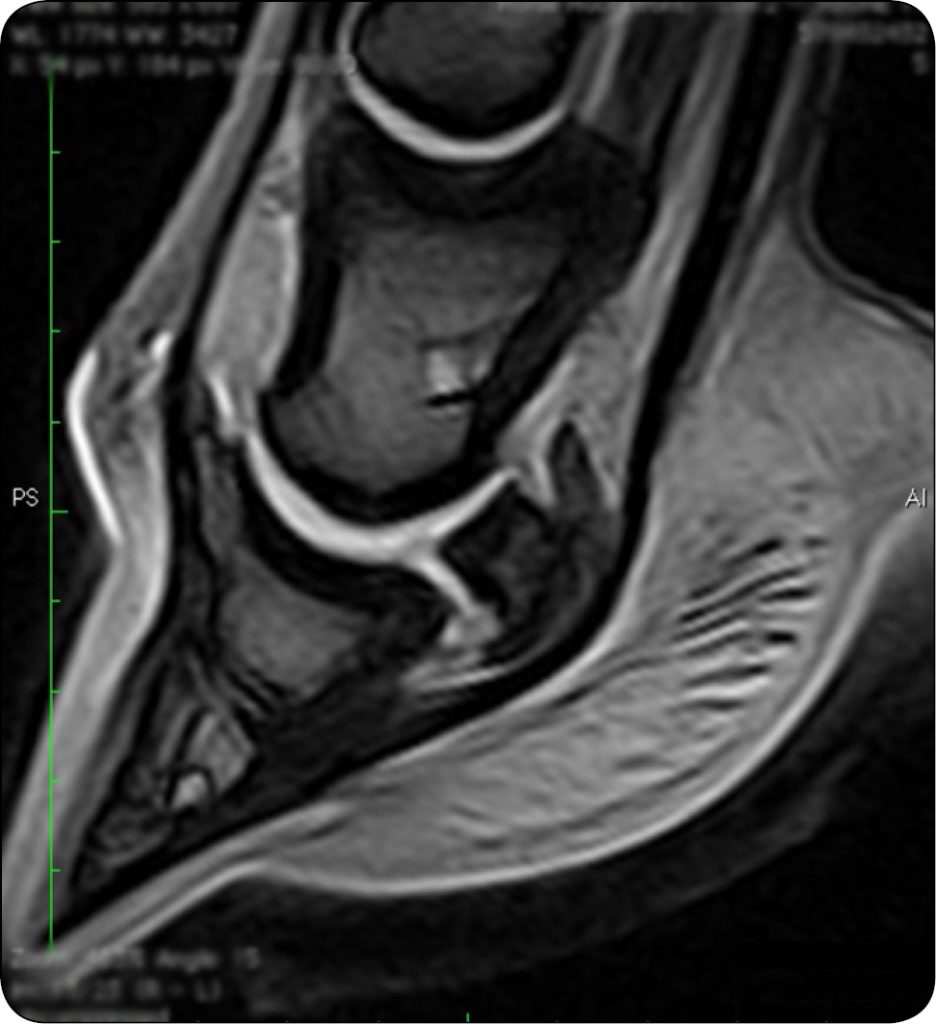

Zmiany dotyczące części zbitej stanowią ubytki, zarówno bardziej powierzchowne, dochodzące do warstwy podchrzęstnej, ale nieprzechodzące przez całą grubość warstwy zbitej, jak i erozje przechodzące przez całą grubość warstwy kory dłoniowej (ryc. 1). Nawiązując do badania, które przeprowadzili Wright i in. (3), nawet 68% ubytków niepełnych lokalizuje się na poziomie grzebienia strzałkowego trzeszczki kopytowej, a ich średnia wielkość wynosi 6,5 mm w wymiarze DV i 15 mm w wymiarze RL (3). Urazy chrząstki włóknistej były diagnozowane wraz ze wzmożoną akumulacją płynu w kaletce kopytowej, co ułatwiało ich wizualizację i sprawiało, że były bardziej wyeksponowane w przekrojach strzałkowych i poprzecznych, głównie w sekwencjach GE i sekwencjach ze stłumieniem tłuszczu. Obejmują one ok. 25-50% grubości chrząstki, z towarzyszącym włóknieniem. Ubytki bardziej powierzchowne stanowią nieregularności podchrzęstne z ogniskami wapnienia i zwiększeniem przestrzeni międzybeleczkowych (2). Obecność zrostów ze ścięgnem mięśnia zginacza głębokiego palca manifestuje się utratą sygnału kaletki kopytowej, ubytkami warstwy zbitej oraz komunikacją ścięgna z trzeszczką kopytową.